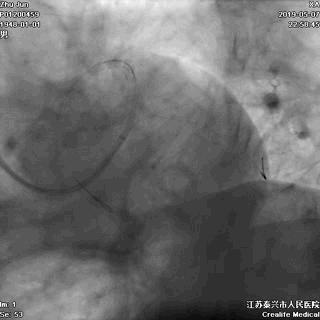

七、最终结果

---即刻效果完美

手术即刻效果完美,患者存活